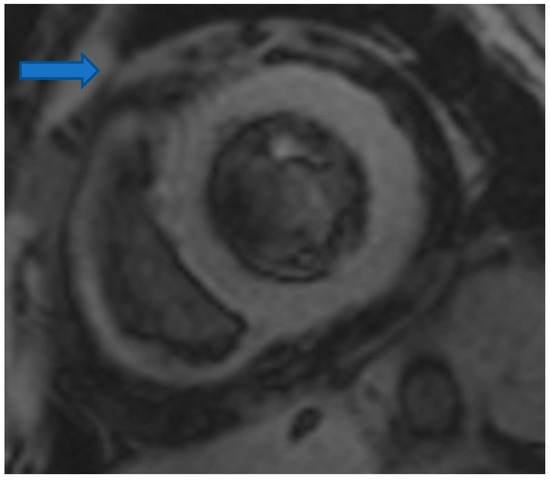

4.5. Myocardial Edema-Fibrosis Assessment